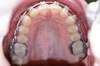

Intra Orale Supérieure